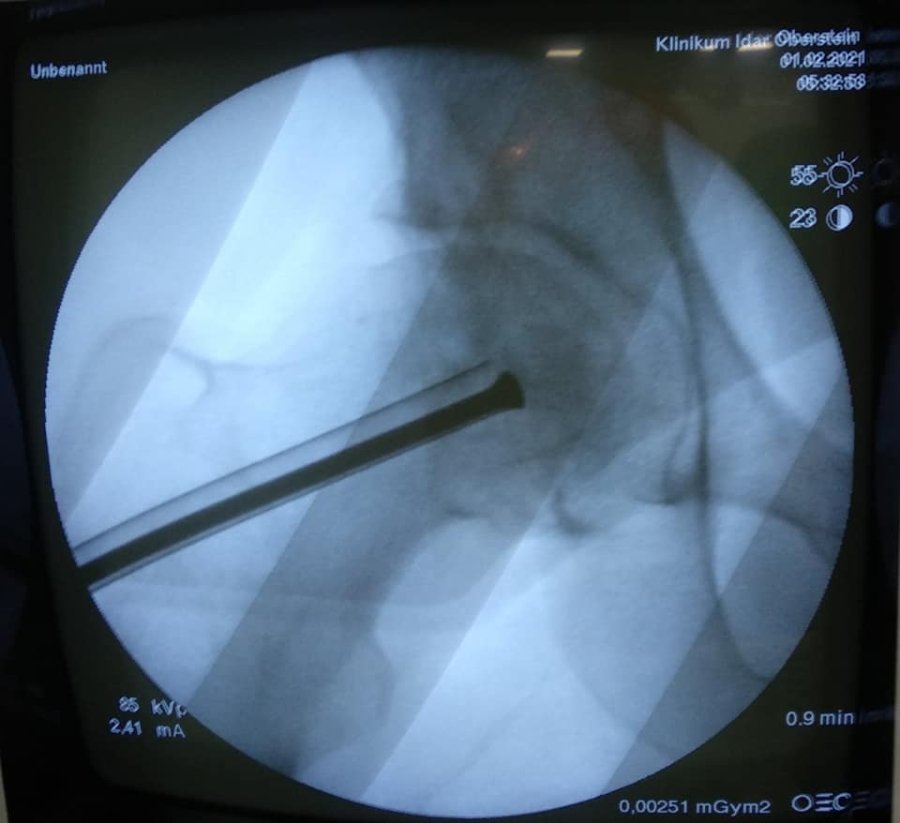

В ході подальшого дослідження в головці правої стегнової кістки виявили кисту розмірами 2*2*2,5 см.

"В ході клінічного розбору було прийняте рішення на користь органозберігаючої операції. Куратор напрямку пухлин та пухлиноподібних захворювань Шевчик Я.В. виконав унікальну операцію: декомпресійну пластику кисти головки стегнової кістки", - йдеться в дописі.

Ця операція полягає у видаленні вмісту кисти, очищенні її стінок та виповнення дефекту кістковим трансплантатом з доступу розміром 3 см.